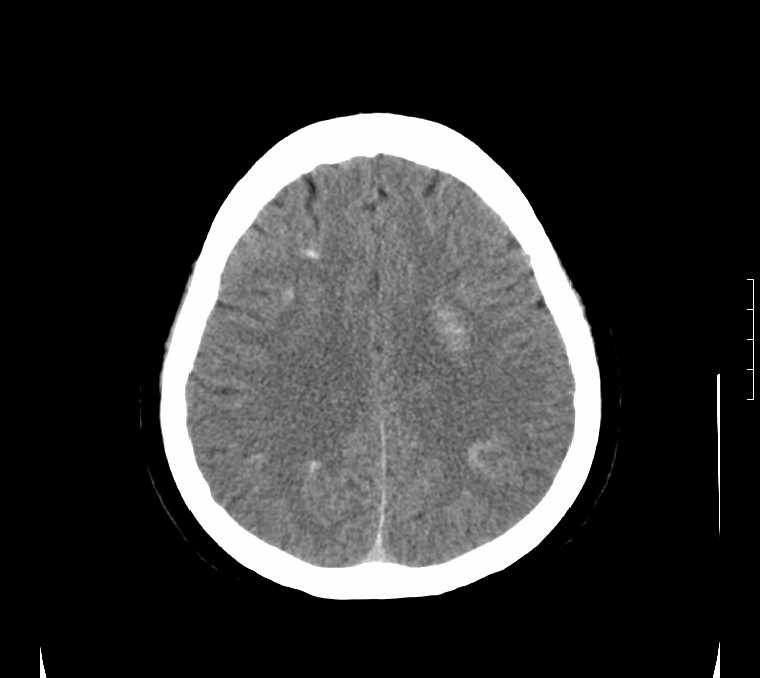

标题: CT24387:看看这例脑部改变!!

老年女性。头晕。

考虑甲旁低所致钙化。

鉴别于特发性家族性脑血管亚铁钙沉着症(fahr`s病)与甲状旁腺机能低下之间,请结合临床及相关实验室检查。